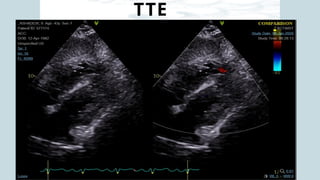

Pre CPB - Apical VSR

Pre CPB – Apical VSR showing multiple jets

across thin apical septum

PRE CPB TEE

oFair LVSF; EF - 30%, CO - 2.8L/m, CI - 1.4L/min/m2

oFair RVSF; RVEF - 26%, RVFAC - 24%, TAPSE – 11 mm

oApical VSR+,

oIt is a complex VSR at the apical ventricular septal level showing

multiple jets across the thin apical septum.

oQp/Qs=2.0

oRWMA+; Apex thinned out. Akinesia of mid mid-anterior and inferior

wall

oMild TR; Mild PAH (RVSP=46)

oMild MR